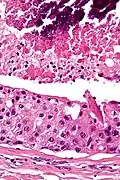

| Low magnification micrograph of a salivary duct carcinoma with characteristic comedonecrosis (left of image) adjacent to normal parotid gland (right of image). H&E stain. | |

Salivary duct carcinoma (SDC) is a rare type of aggressive cancer that arises from the salivary glands.[1] It is predominantly seen in men and, generally, has a poor prognosis.[2] Other high grade carcinomas can mimic SDC. About 40-60% of SDC arise in pleomorphic adenomas.[3] Most, if not all, SDCs express androgen receptor by immunohistochemistry.[4] Therapeutically relevant genetic alterations include ERBB2/Her2 amplification, PIK3CA and/or HRAS mutations.[5][6]

Their histologic appearance is similar to ductal breast carcinoma.